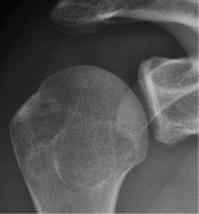

需要在肩关节内旋位、中立位、外旋位时分别拍摄3张正位X线,来评估有无Hill-Sachs损伤。

外旋位

通过正位X线看关节盂下方是否存在撕脱性骨折或者是轮廓的丢失。

正常

关节盂下缘撕脱性骨折

关节盂下缘轮廓丢失

如在肩关节外旋位的正位X线上能看到Hill-Sachs损伤,则评分应为2分;

如果正位X线上能看到关节盂下缘的轮廓丢失,则同样应为2分。